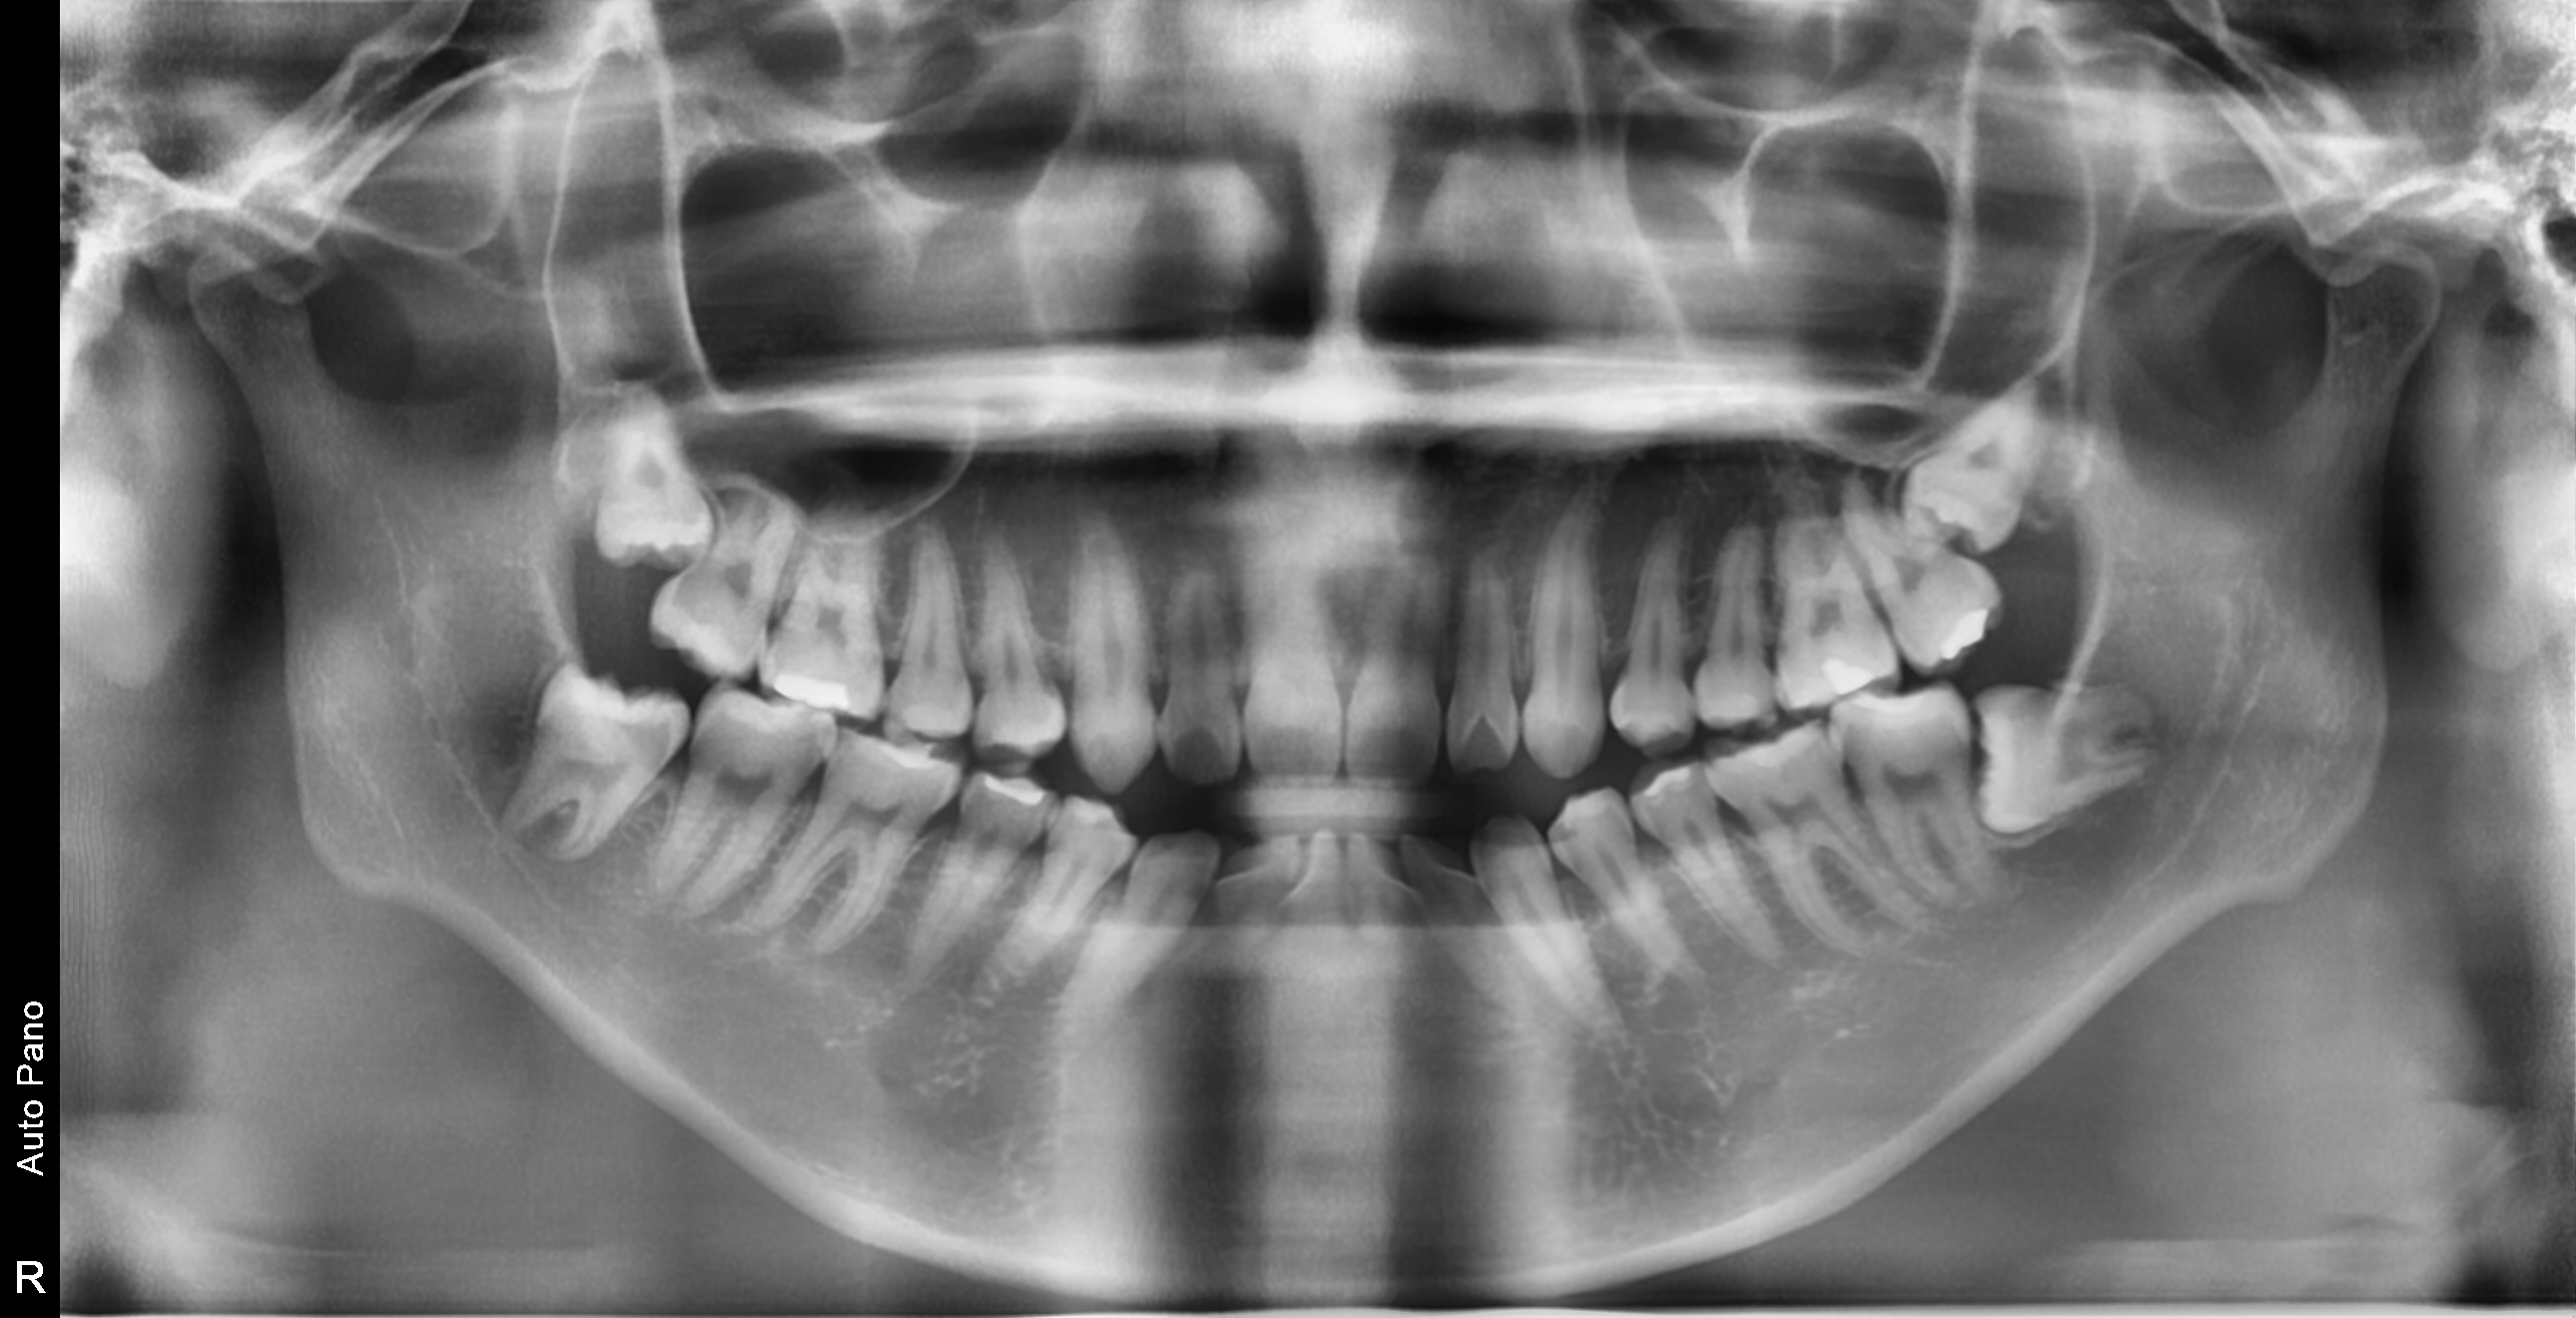

대학병원급 난이도 발치

일반 치과에서 "큰 병원 가보세요", "전문병원에서 빼세요" 이런 말 들어보셨나요?

복잡한 매복 사랑니 - 잇몸 속 깊이 묻혀있어도 OK

신경 근접 사랑니 - 신경 손상 걱정 없는 안전한 발치

수평 매복 사랑니 - 옆으로 누워있는 어려운 케이스도 가능

2,700건 이상의 발치 경험으로

대학병원 수준의 난이도도 안전하게 해결합니다

난이도 높은 사랑니도 뽑을 수 있나요?

네, 가능합니다. 경성 메디스 치과는 2,700건 이상의 발치 경험과 대학병원급 난이도 발치가 가능한 시스템을 갖추고 있습니다. 수평매복, 완전매복 등 일반 치과에서 큰 병원을 권유하는 어려운 케이스도 3D CT 정밀 진단으로 안전하게 발치합니다.